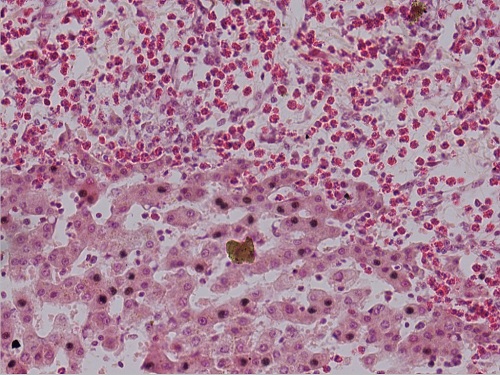

蛔虫性肝硬变3(肝小叶间有大量嗜酸性粒细胞,有蛔虫虫体)10X40